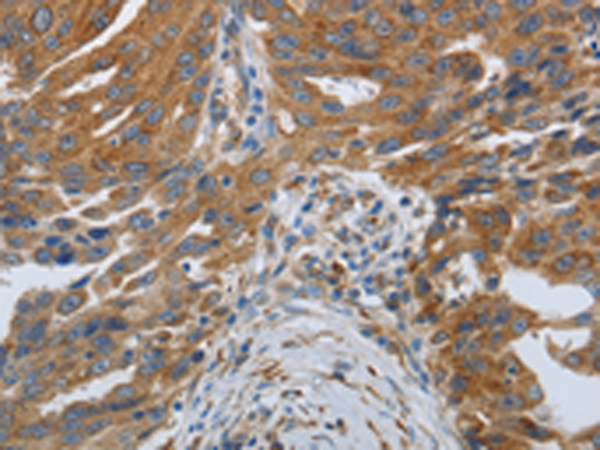

分类: 科研抗体货号: P11133别名: MTK1; MEKK4; MAPKKK4; PRO0412应用: IHC反应种属: Human